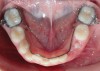

Fig 11. Severely constricted maxilla/high-vaulted palate.

Figure 11

Tongue and thumb pressures also contribute to a high-vaulted palate, which can lead to mouth breathing (Figure 11).31 Additional risks exist for infection and callus development on the thumb. Ideally, the child should quit this habit by age 4, before permanent occlusal changes develop.32 Quitting can be achieved through positive reinforcement and by offering the child comfort during thumb-sucking triggers. The use of bitterants (eg, Mavala Stop, Thum, Control-It!), which are painted on or rubbed into the thumb, is another option.33 A habit breaker appliance may also be utilized if these techniques are unsuccessful. Devices such as a palatal crib, rake, or bluegrass appliance interfere with the thumb and tongue habits and allow the bite to passively close.34 The author recommends utilizing a habit breaker appliance for 6 to 9 months and maintaining reinforcement for a few months once the habit is eliminated (Figure 12 through Figure 14).